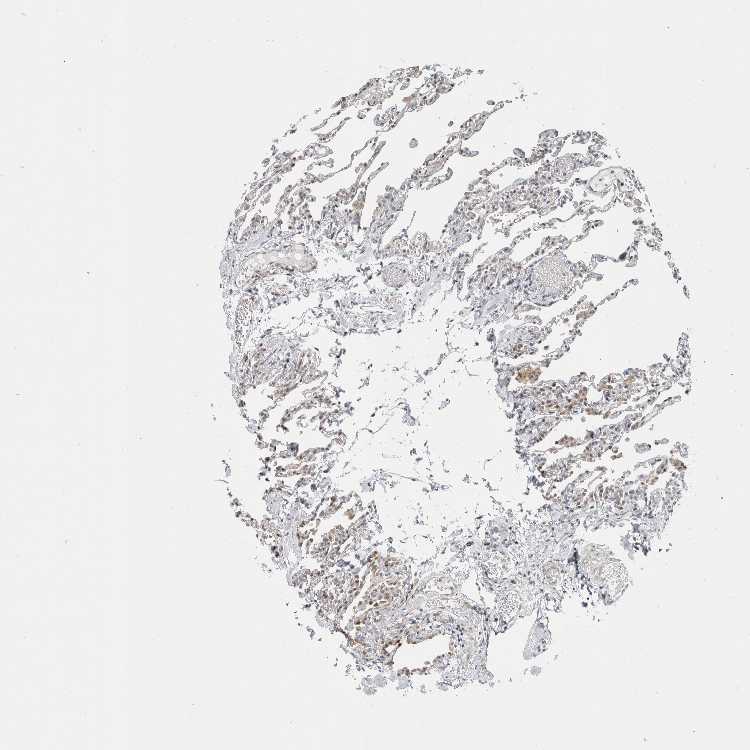

LUNG - Antibody stainingi

Antibody staining in the annotated cell types in the current human tissue is reported as not detected, low, medium, or high, based on conventional immunohistochemistry profiling in selected tissues. This score is based on the combination of the staining intensity and fraction of stained cells.

Each image is clickable and will lead to virtual microscopy that enables deeper exploration of all samples and also displays staining intensity scores, fraction scores and subcellular localization as well as patient and tissue information for each sample.

Antibody HPA005695Antibody CAB022068Antibody CAB035999Antibody CAB080052Antibody CAB080054Antibody CAB080098

Alveolar cells Not detectedLowMediumMediumNot detectedNot detected

Macrophages LowNot detectedMediumNot detectedNot detectedNot detected